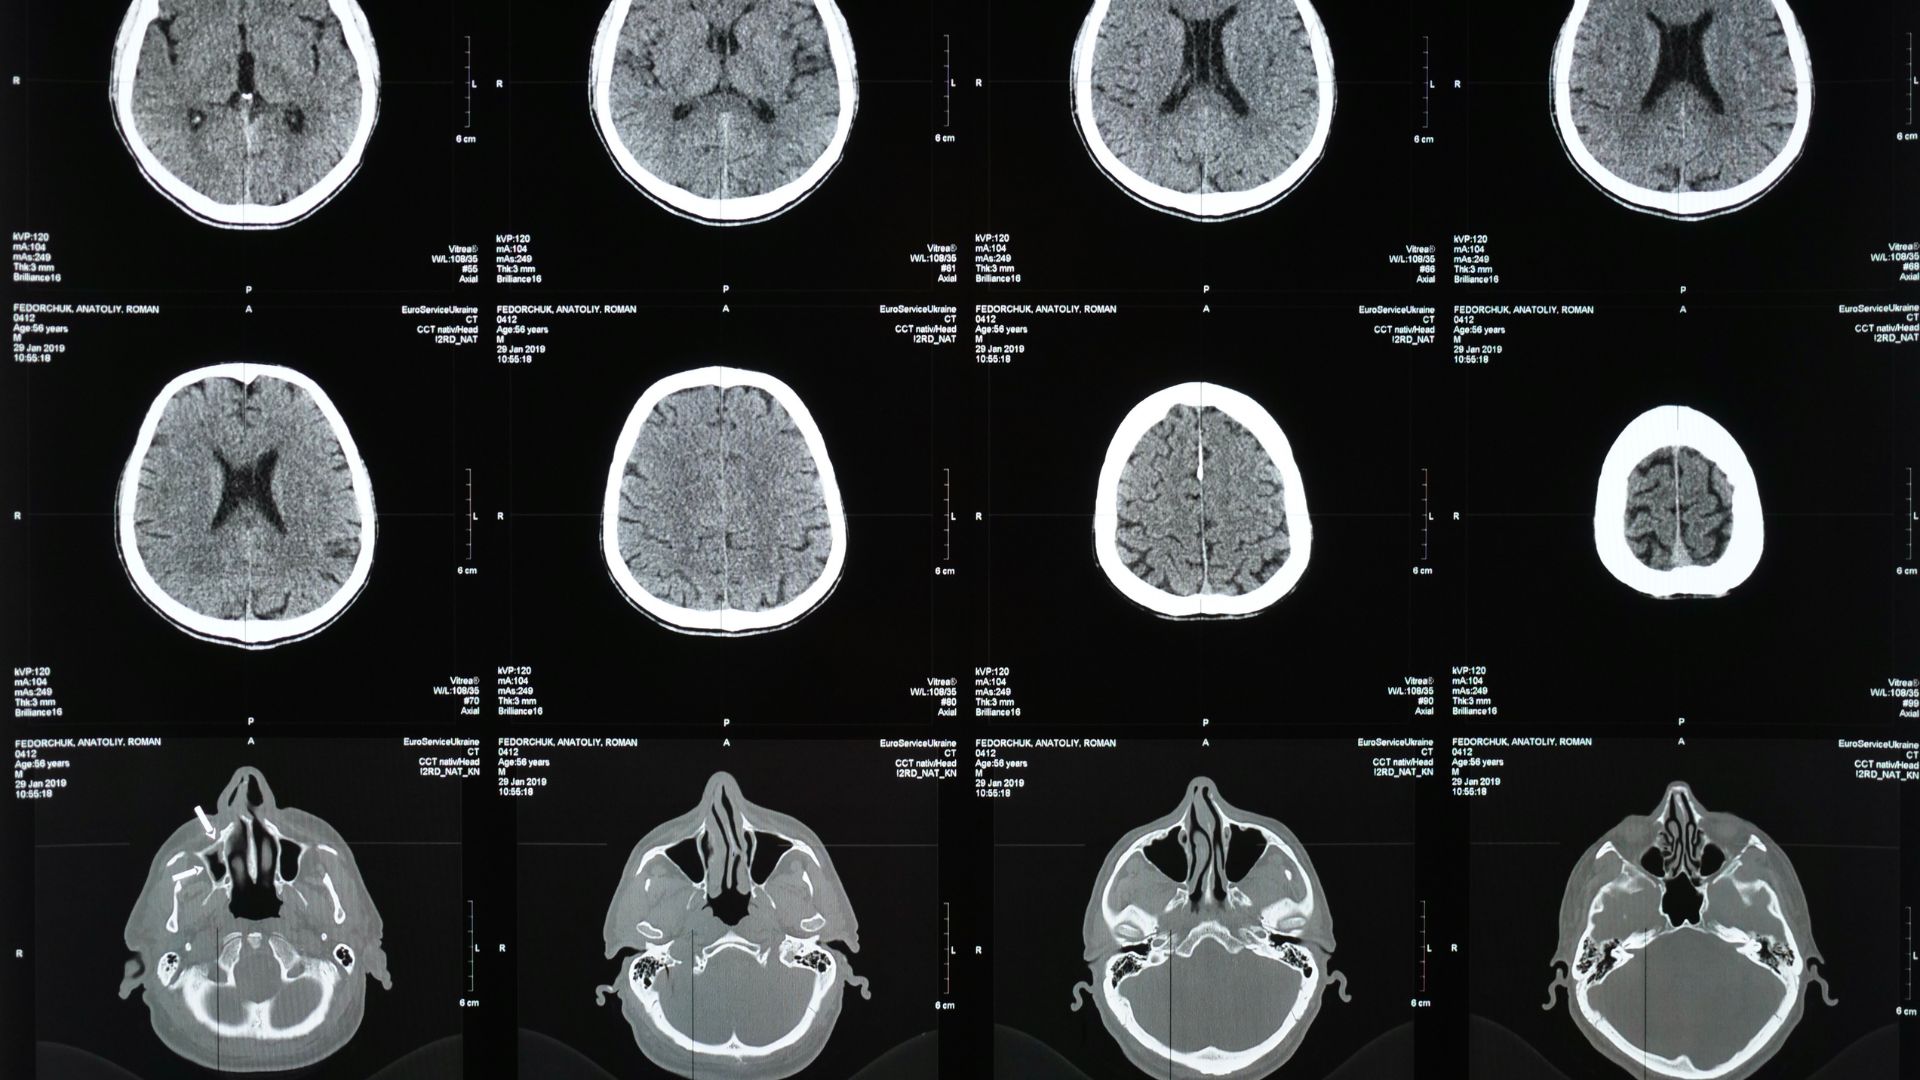

- Siêu âm thai: Đây là công cụ chẩn đoán chính xác nhất, cận lâm sàng này cho phép quan sát hình ảnh cột sống và não của thai nhi để phát hiện các bất thường về cấu trúc.

- Chọc dò dịch ối: Bác sĩ lấy một mẫu dịch ối để kiểm tra nồng độ AFP và acetylcholinesterase, giúp khẳng định chẩn đoán. Sau khi sinh, các xét nghiệm hình ảnh như chụp MRI hoặc CT có thể được thực hiện để đánh giá mức độ nghiêm trọng của tổn thương.